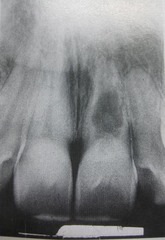

Unilocular (radiographic terms used to describe lesions in bone)

Front

Having one compartment or unit that is well defined or outlined, as in a simple radicular cyst.